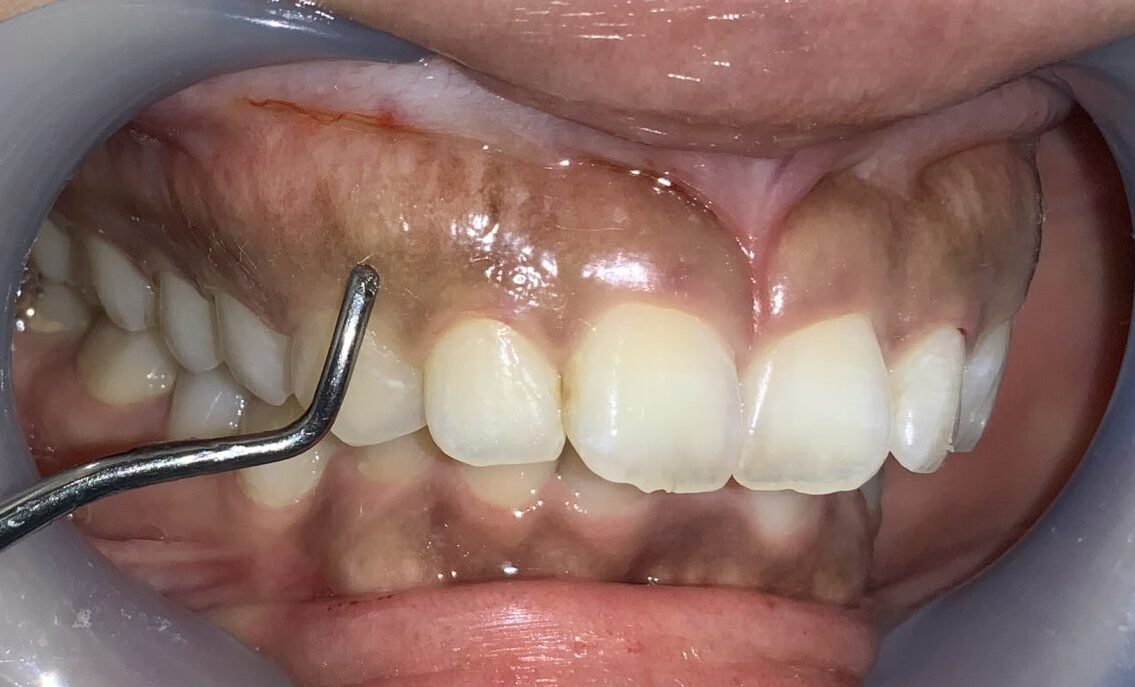

少し小さい隣の歯です。

歯ぐきは薄いようですが、歯ぐきの被っている量はたくさんあります。

今度は犬歯です。この歯は大きく切り取ってしまうと「八重歯」みたいになってしまうので、歯ぐきを整形するときに注意が必要な歯です。

歯ぐきが被っている量や厚みはたくさんあります。

患者様のご希望により、4番目の小臼歯も整形します。費用の追加はありません。

奥歯になりますが、綺麗に整えることが出来ます。